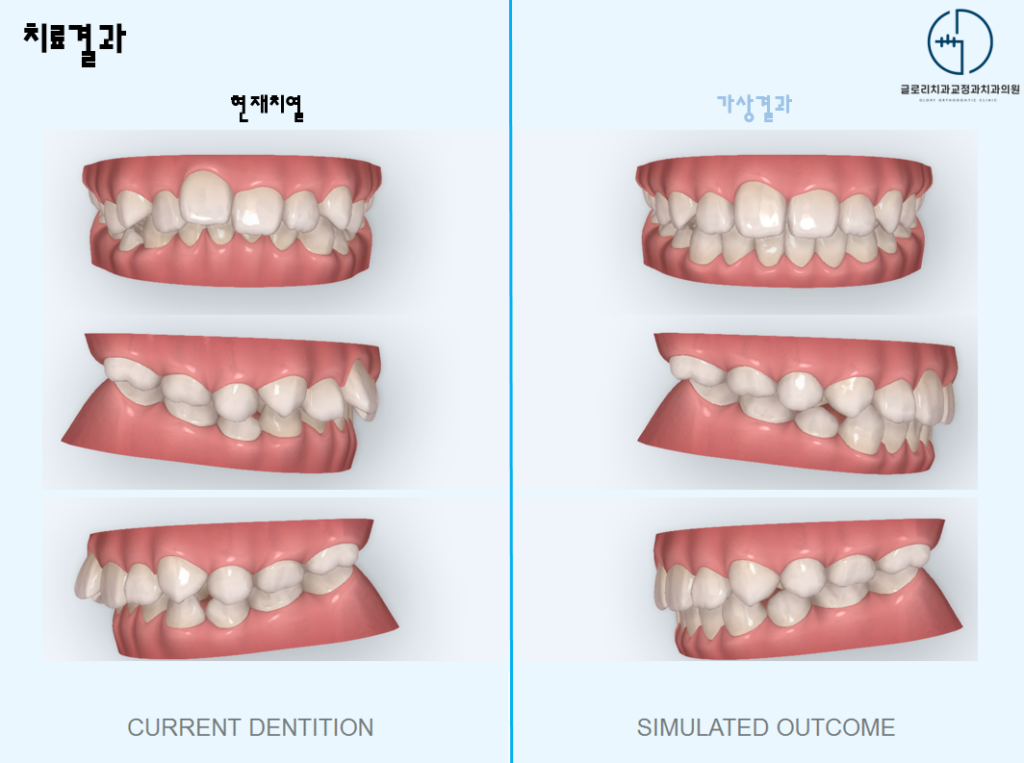

중랑구 교정치과 에서는 클린체크 시뮬레이션을 통해 앞으로 나올 영구치 위치를 예상하고 그에 맞춰 악궁을 확장하거나 치아 배열을 유도합니다.

치료 후에는 영구치들이 본래의 자리를 되찾아 가면서 치열이 가지런하게 마무리됩니다.